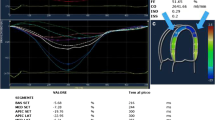

Speckle-tracking echocardiography, myocardial work and myocardial contraction fraction are new echocardiographic techniques in CA. These techniques can be used in the possible diagnosis and prognosis prediction of CA (Fig. 3 and Table 1).

Application of Echocardiography in CA. A The apical view of the two-dimensional echocardiography showed the ventricular hypertrophy. B The three-chamber view of the two-dimensional echocardiography showed the hypertrophy and “granular” of the LV interventricular septal wall. C The tissue Doppler showed a decreased mitral annular motion. D The two-dimensional speckle-tracking echocardiography showed apical sparing of the LV segmental longitudinal strain. E, F LV pressure-strain myocardial work showed an apical sparing of the LV segmental myocardial work and myocardial efficiency

Myocardial work

Based on the measurement of myocardial strain, myocardial work is a parameter that considers the effects of LV deformation and afterload during the assessment of LV pressure, providing references for the evaluation of cardiac function (Fig. 3E, F) [55]. The LV pressure-strain loop, integrating the measurement of myocardial strain and LV pressure, is a standard evaluation method of myocardial work. It can better reflect the early changes in LV systolic functions among HFpEF patients with different diastolic functions than GLS. Clemmensen et al. [56] revealed that CA patients’ LV myocardial work index (LVMWI) was significantly lower than the average population, which could increase through exercise. However, the constantly declining LV myocardial work efficiency (LVMWE) suggested the low utilization rate of myocardial energy in CA patients. By assessing the cardiac load of patients with CA and HFpEF through LVMWE, Palmiero et al. [57] found that the global work efficiency (GWE) was lower in AL-CA patients compared with ATTR-CA patients, implying that the myocardial dysfunction in AL-CA patients was more evident. They also discovered that AL-CA and ATTR-CA could be appropriately distinguished when GWE < 86.5%, with a sensitivity and specificity of 80.0% and 66.7%, respectively [57]. When LVMWI < 1039 mmHg%, the risk of all-cause mortality in CA patients visibly increased with a hazard rate of 6.4 (95%CI: 2.4–17.1) [58]. Low LVMWE is the potential predictor of adverse cardiovascular events in CA patients [59], and patients with LVMWE < 89% are faced with a high risk of all-cause mortality [60].